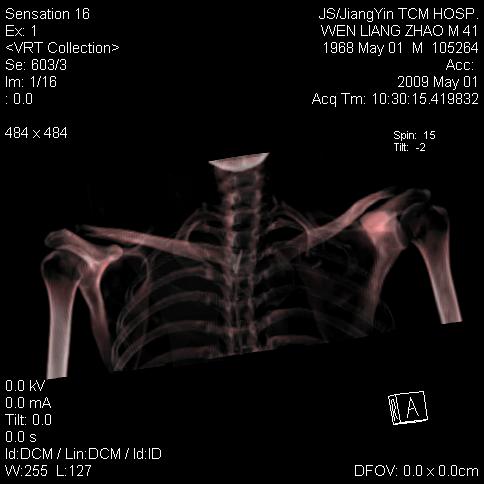

标题: CT19762:左侧喙突处压痛二年。考虑骨样骨瘤。 [打印本页]

标题: CT19762:左侧喙突处压痛二年。考虑骨样骨瘤。

左侧喙突处压痛二年。考虑骨样骨瘤。

病灶外缘膨胀明显,灶缘硬化较少,结合病史较符合骨母细胞瘤,其他亦不排除如软骨及软骨母细胞瘤等(病灶形态,成份较符合,发病部位也符合,只是年龄较大),骨样骨瘤多有较明显的自发性痛,且夜间痛明显,病史为压痛两年,不太符合.